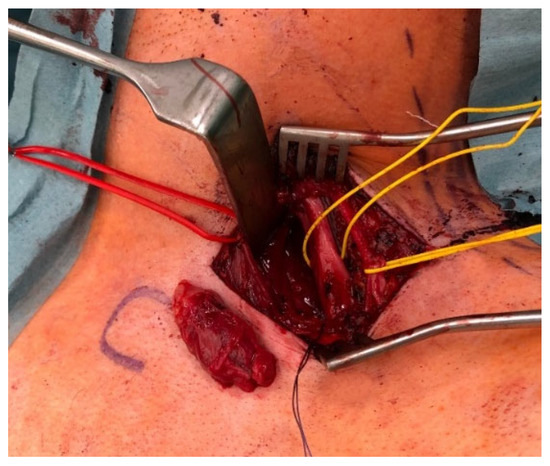

Background and Clinical Significance: Neurofibromatosis type 1 (NF1) predisposes individuals to various peripheral nerve sheath tumors (PNSTs), including benign neurofibromas, malignant peripheral nerve sheath tumors (MPNSTs), and intermediate lesions known as atypical neurofibromatous neoplasms of uncertain biologic potential (ANNUBP), previously often termed atypical neurofibroma. These atypical lesions are considered premalignant precursors to MPNST. Case Presentation: We present the case of a 33-year-old male with NF1 who developed a rapidly growing, painful mass in his right calf. Clinical examination revealed signs consistent with NF1. Magnetic resonance imaging showed a large, heterogeneous mass in the lateral compartment. Biopsy revealed a neurofibroma with hypercellularity, moderate atypia, scarce S100 positivity, focal CD34 positivity, and an elevated Ki-67 proliferation index of 10–12%, consistent with ANNUBP. The patient underwent wide surgical resection, including the fibula and peroneal muscles. At the 30-month follow-up, there was no local recurrence, though the patient had a mild residual limp. Discussion: This case highlights the clinical presentation, diagnostic features, and management considerations for ANNUBP in NF1, emphasizing the importance of recognizing warning signs and the role of pathology in guiding treatment for these high-risk precursor lesions. Full article

Figure 1